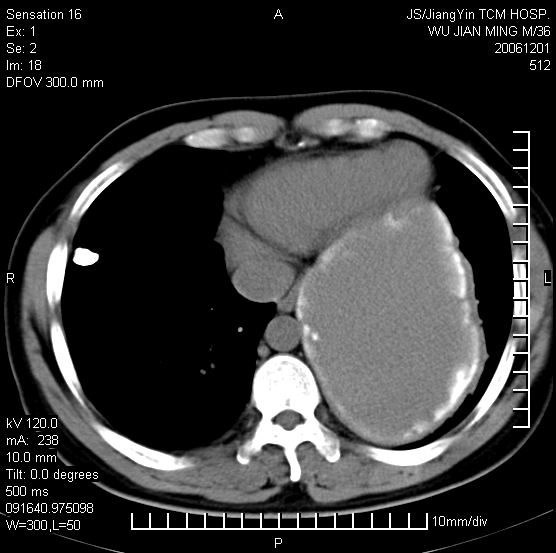

以下是引用dyqct在2006-12-1 21:17:00的发言:[br]左心缘旁及后肋膈窦区见巨大椭圆形混杂密度肿块,周围见大小不等斑片状钙化,内部无强化,周围包膜轻度强化,心脏明显受压变形,即明显占位效应,肿块广基与心包、膈相连。肝、脾内、肝门见多数小结节状钙化影。[br]考虑:1、左心缘旁及后肋膈窦区慢性包裹性胸膜炎(结核性);[br] 2、肝、脾及肝门淋巴结核已钙化。[br]

以下是引用zrs在2006-12-2 17:28:00的发言:[br]肺内、肝脾内虽有钙化,但不支持结核性胸胸膜炎包裹,而支持寄生虫感染![br][br]

以下是引用zyx168在2006-12-2 10:10:00的发言:[br][br]肝脾肺内多发钙化灶